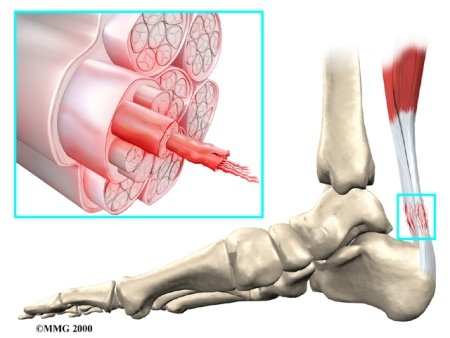

Tendons connect muscle to bone. A tendon is made of material called collagen. Collagen is a key building block of the body. Collagen is considered a connective tissue because it forms tough strands that are like the strands of a nylon rope. Like the strands in a rope, the strands of collagen line up. The more strands, and the better they line up, the stronger they are. The tendon is wrapped in a thin, slippery covering called the tendon sheath. The tendon sheath allows the tendon to slide easily against the tissues around it.

Many parts of the tendon can be injured. Tendon problems can involve the area where the tendon attaches to the bone, the tissue that surrounds the tendon (the tendon sheath), or the main tissues of the tendon. Doctors use different terms to refer to injuries of different parts of the tendon.

Achilles Tendonitis

The tendon sheath, the tissues of the tendon, and the attachment to the bone can all become injured in the:

Achilles Tendon

found in the lower leg. Damaged Achilles tendons carry a higher risk of rupturing because of the weight they bear while standing and walking.

Some researchers think that a decreased blood supply to the tendons can cause the tendon damage in tendonosis. The decreased blood supply does not allow the tendon to get enough oxygen from the blood. This leads to a condition where the tendon degenerates. The collagen material that makes up the tendon actually becomes weaker and loses its nylon rope appearance. This type of degeneration has been noted in the rotator cuff around the shoulder, in the Achilles tendon in the heel and in the tendons of the elbow.